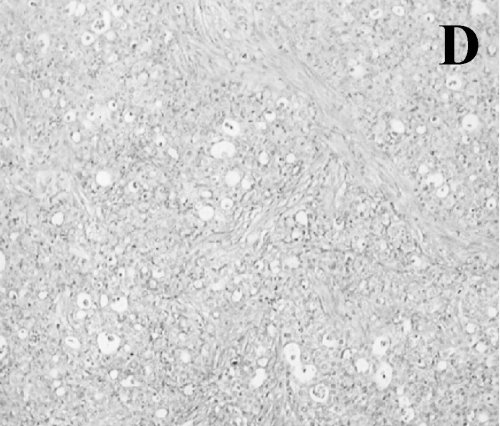

Figure 2. A case from the

SCI group. A. Appearance of the right lymph node. B. Necropsied

lymph node specimen cut sagitally. C. Histopathologic view of the lymph node (H&E, 100x). |

Follow-up,

Local Recurrence and Findings in the Necropsy

In the follow-up, neither the SCI nor the STI group showed local recurrence at the site of implantation. Thirteen SCI hamsters (86.7%) developed right axillary lymph node metastasis (Table 1), which was palpable between 4 and 12 weeks after the resection. This lymph node in the early stage was movable. After approximately 2 weeks, it became adhered to deep tissue and grew to 6 cm in diameter. When the lymph node reached this size, the animals died. In the necropsy, there was no local recurrence, or macroscopic internal-organ metastases. The metastatic axillary lymph node showed central necrosis (Figure 2). All lymph nodes were confirmed as metastasis at the histopathological and molecular level. The lungs, liver and pancreas did not show any metastases. The remaining two animals of this group without axillary lymph node metastasis did not have any metastases in their internal organs. The cause of death was unknown.